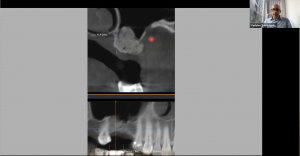

Операционный микроскоп является штатным оборудованием любого стоматологического кабинета. Работа с микроскопом позволяет хирургу стоматологу избавить своих пациентов от необоснованных страданий, а так же работать эргономично, что сохраняет здоровье доктора на долгие годы. Информация, полученная на данном вебинаре, позволит Вам лучше разобраться с необходимыми характеристиками микроскопа и знать основные понятия при работе с таким оптическим устройством. Материал вебинара предоставляет фактические рекомендации по работе хирурга-стоматолога с различным уровнем навыка, от старта до микрохимрургических манипуляций. Дан обзор некоторых возможных, при работе с операционным микроскопом, мало-инвызивных методов аугментации кости и манипуляций мягкими тканями.